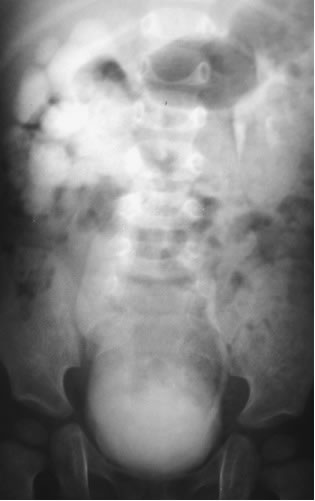

Обструктивная форма:

Приведены данные при уретероманометрическом исследовании.

При этом отмечается значительное снижение внутримочеточникого

давления и отсутствие сокращений мочеточника при необструктивной

форме мегауретера.